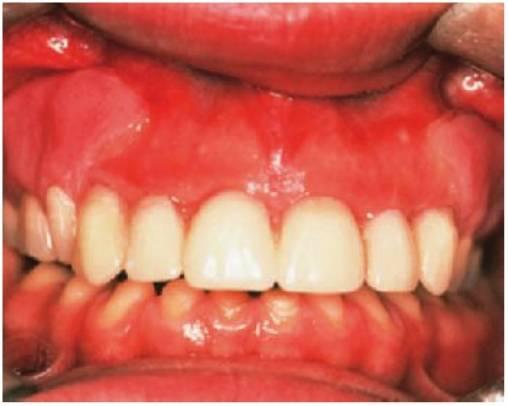

Amelogénesis imperfecta

El término amelogénesis imperfecta (fig. 9.25) suele aplicarse a defectos hereditarios del esmalte que afectan tanto a los dientes temporales como a los permanentes. La definición implica una historia familiar, pero en la práctica parece razonable ampliar esta definición para incluir los casos esporádicos y aquellos otros en los que los defectos del esmalte se asocian a manifestaciones extraorales, como ocurre en algunos síndromes (es decir, hipoplasia dérmica focal o síndrome trico-dento-óseo).

Fenotipos

Los fenotipos oscilan desde el esmalte (fino) marcadamente hipoplásico, uniformes (con espacios entre los dientes) o irregulares (dando lugar a pozos o surcos) hasta los diferentes grados de hipomineralización (esmalte muy mal formado) con alteraciones en su color y traslucidez. En muchos casos, la hipoplasia y la hipomineralización se presentan juntos. El color del esmalte refleja con claridad el grado de hipomineralización del mismo: cuanto más oscuro se presente el tono, más grave será la desmineralización.

En la amelogénesis imperfecta ligada al cromosoma X, las mujeres presentan franjas ver ticales de esmalte alterado como signo de lyonización (v. hipótesis de Lyon, descrita en este mismo capítulo). Pueden ser surcos verticales (debido a la hipoplasia) y/o bandas verticales de esmalte con el color o lucidez alterados (debido a la hipomineralización), o bien una combinación de ambos. En estas familias no existirá transmisión de varón a varón, pero las mujeres heterocigóticas pueden transmitir el rasgo a niños del mismo sexo.

En algunos pacientes afectados por amelogénesis imperfecta, los dientes no llegan a erupcionar, se cree que debido a una alteración del órgano del esmalte y sufren una reabsorción de sus coronas. En algunos casos (más del 50%) se observa una mordida abierta esquelética anterior.